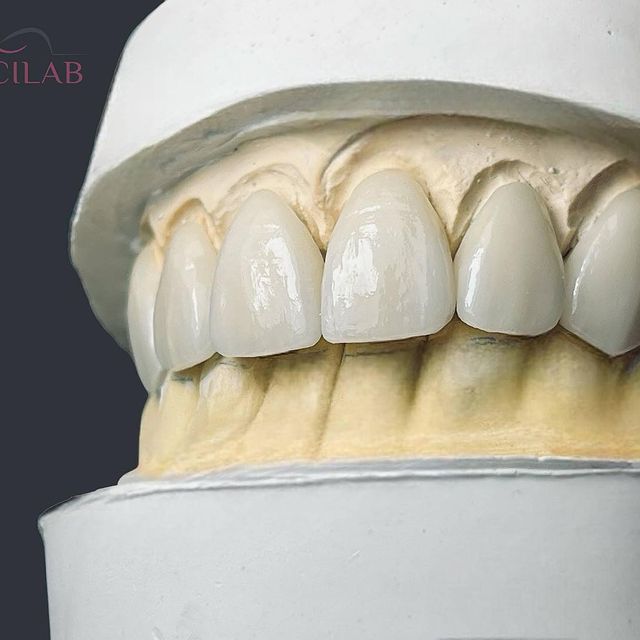

Emcilab Laboratorio Dental

Donde la precisión y la estética se fusionan para crear nuevas sonrisas….

Soluciones avanzadas en restauraciones dentales para la odontología.

Soluciones avanzadas en restauraciones dentales para la odontología.